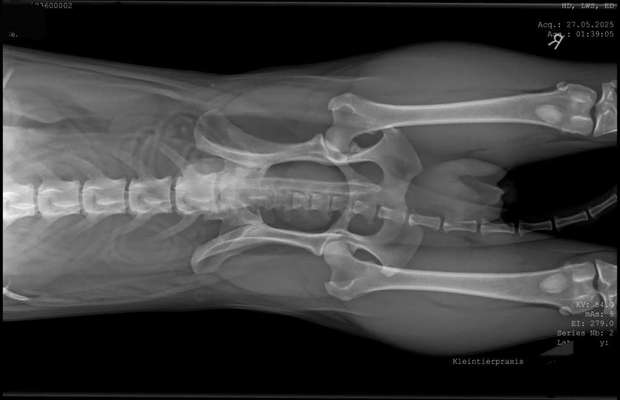

Röntgen wurde ja gemacht und sowohl unser Tierarzt als auch ein Orthopäde haben sich das angeschaut.

Ich hatte es weiter unten schon mal geschrieben, unserem Tierarzt ist gar nichts aufgefallen, der Orthopäde meinte Ninos seine Hüftgelenke wären nicht so super, dürften ihm aber eigentlich keine Schmerzen verursachen.

Ich finde auf dem Röntgenbild sieht man, dass die Knochen der Rute schon zu seiner Seite gebogen sind.

hier sieht man das wie die Rute zur Seite geht und nicht in der Mitte ist.

Oder sieht das immer so aus? Bei geraden Ruten ist das sicher eine Gerade.